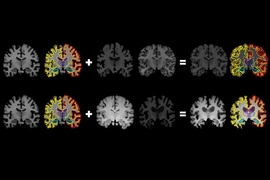

Deep learning-based, fully automated, pediatric brain segmentation

Imaging techniques are used to capture anomalies of the human body. The captured images must be understood for diagnosis, prognosis and treatment planning of the anomalies. Medical image understanding is generally performed by skilled medical professionals. However, the scarce availability of human experts and the fatigue and rough estimate procedures involved with them limit the effectiveness of image understanding performed by skilled medical professionals. Convolutional neural networks (CNNs) are effective tools for image understanding. They have outperformed human experts in many image understanding tasks. This article aims to provide a comprehensive survey of applications of CNNs in medical image understanding. The underlying objective is to motivate medical image understanding researchers to extensively apply CNNs in their research and diagnosis. A brief introduction to CNNs has been presented. A discussion on CNN and its various award-winning frameworks have been presented. The major medical image understanding tasks, namely image classification, segmentation, localization and detection have been introduced. Applications of CNN in medical image understanding of the ailments of brain, breast, lung and other organs have been surveyed critically and comprehensively. A critical discussion on some of the challenges is also presented.

5 CNN applications in medical image segmentation

CNNs have been applied to implement efficient segmentation of images of brain tumors, hearts, breasts, retina, fetal abdomen, stromal and epithelial tissues.

5.1 Brain tumors

MRI is used to obtain detailed images of the brain to diagnose tumors. Automatic segmentation of a brain tumor is very challenging because it involves the extraction of high level features.

5.1.1 Small kernel CNN

Patch-wise training and use of small filter sizes ( \(3\times 3\) ) was proposed for segmentation of gliomas in [ 54 ]. This provided an advantage of deep architecture, while retaining the same receptive fields. Two separate models were trained for high and low gliomas. High glioma model consisted of eight conv layers and three dense layers. Low glioma model contained four conv layers and three dense layers. Maxpooling was used along with dropout for dense layers. It ranked fourth in the BRATS-2015 challenge. Data augmentation was achieved by rotation which enhanced the performance of segmentation of gliomas.

5.1.2 Fully blown CNN

Fully blown MRI two-dimensional images enhances performance of segmentation of sub-cortical human brain structure. This was shown in [ 66 ]. The proposed model applied Markov random field on CNN output to impose volumetric homogeneity to the final results. It outperformed several state-of-the-art methods.

5.1.3 Multipath CNN

Two pathways, one for convolution and the other for deconvolution, enhances segmentation output was shown in [ 8 ]. The model was used for automatic MS lesions segmentation. The model had convolutional pathway consisting of alternating conv, pool layers, and a deconvolutional pathway consisting of alternate deconv layer and unpooling layer. The pretraining was performed by convolutional RBMs (convRBM). Both pretraining and fine training were performed on a highly optimized GPU-accelerated implementation of three-dimensional convRBMs and convolutional encoder networks (CEN). It was compared with five publicly available methods and established as comparison reference points. The model performance was evaluated using evaluation metrics DSC, TPR and FPR. TPR and FPR achieved were comparatively better than the previous models developed. However, it achieved lesser DSC in comparison to other methods.

5.1.4 Cascaded CNN

In case of imbalanced label distributions, two phase training could be used. Global contextual features and local detailed features can be learned simultaneously by two-pathway architecture for brain segmentation and was proposed in [ 25 ]. The advantage of two-pathway was, it could recognize fine details of the tumor at a local scale and correct labels at a global scale to yield a better segmentation. Slice-by-slice segmentation from the axial view due to less resolution in the third dimension was performed. The cascaded CNN achieved better rank than two-pathway CNN and was ranked second at the MICCAI BRATS-2013 challenge. The evaluation metrics used were DSC, specificity and sensitivity and the obtained values were \(79\%, 81\%\) and \(79\%\) . The time taken for segmentation was between 25 s and 3 min.

5.1.5 Multiscale CNN

In case of brain tumor segmentation, a multiscale CNN architecture for extracting both local and global features at different scales was proposed in [ 80 ]. The model performed better due to different features extracted at various resolution. The computation time was reduced by exploiting a two-dimensional CNN instead of a three-dimensional CNN. Three patch sizes \(48\times 48\) , \(28\times 28\) and \(12\times 12\) were input to three CNNs for feature extraction. All the features extracted were input to the FC layer. Evaluation of the model was by DSC and accuracy. The model performance was almost as stable as the best method with an accuracy of nearly \(90\%\) .

5.1.6 Multipath and multiscale CNN

Twopath and multiscale architecture were also explored for brain lesion segmentation by [ 37 ]. The model exploited smaller kernels to get local neighbour information and employed parallel convolutional pathways for multiscale processing. It achieved highest accuracy when applied on patients with severe traumatic brain injuries. It could also segment small and diffused pathologies. Three-dimensional CNN produced accurate segmentation borders. FC three-dimensional CRF imposed regularization constraints on CNN output and produced final hard segmentation labels. Also, due to its generic nature, it cold be applied to different lesion segmentation tasks with slight modifications. It was ranked first in the stroke lesions ISLES-SISS-2015 challenge.

Advantages of multipath and multiscale CNN was exploited for automatic segmentation of analytical brain images in [ 49 ]. The bigger kernel was used for spatial information. A separate network branch was used for each patch size, and only the output layer was shared. Mini batch learning and RMSprop were used to train the network with ReLU and cross entropy as the cost function. Automatic segmentation was evaluated using the DSC and mean surface distance between manual and automatic segmentation. It achieved accurate segmentation in terms of DSC for all tissue classes. The CNN approaches for brain segmentation discussed above are summarized in Table 11 .